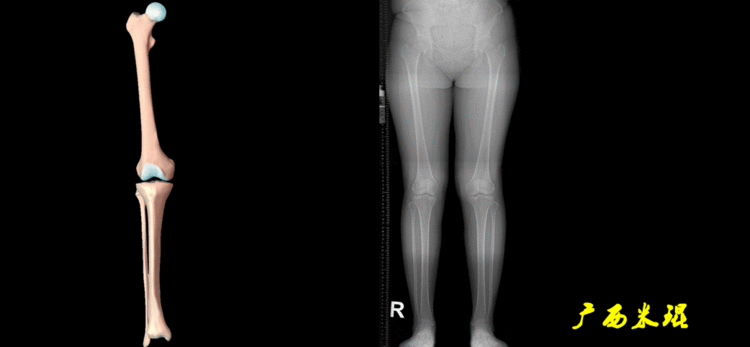

下肢力线及相关角度测量的前提是必须拍摄标准的站立位也就是负重位的下肢全长片。目前这样的照片都是放射科的技师在电脑上拼接出来的,大部分医院的DR都能够做到这一点。

患者直立于摄影架上,后背贴近摄影架,双手自然下垂,膝关节尽量伸直,足部与双肩同宽,要求投照时双髌骨朝正前方,通常患者双足尖应平行向前即可。

提醒一下大家,拍摄过程中应避免下肢的外旋和内旋。如果有一侧肢体短缩时,投照应当用脚垫垫高短缩肢体,使骨盆保持水平,这样下肢短缩测量才精确。如果有肢体旋转畸形时,还是以髌骨朝前为标准,虽然此时双足可能不能保持平行。

二、下肢全长片的基本要求

无论如何,拍摄出来的下肢全长片必须包含髋关节中心、膝关节中心及踝关节中心,否则对临床是无用的。有了一张下肢的全长照片,我们需要确定下肢关节的中心点,通过中心点画出下肢的各种轴线,然后利用轴线与关节线的相交得出各种所需要的角度。